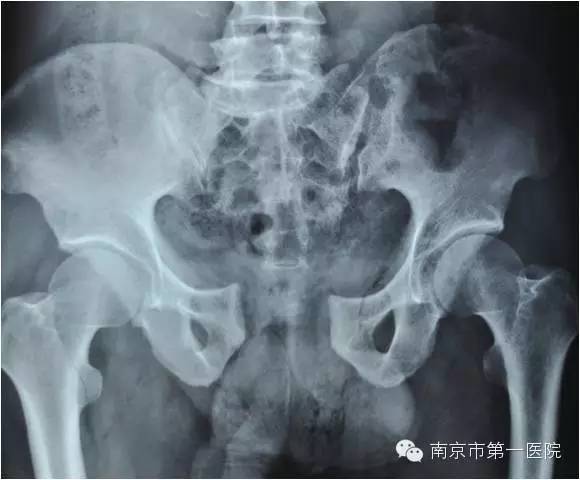

随后,老张第一时间被送到当地医院进行了简单处理,处理完又立刻转到南京市第一医院进行进一步抢救。据了解,小卡车大约1.5吨重,受伤的部位在骨盆,由于受到碾压和挤压,导致骨盆内的肌肉撕裂、血管损伤,骨盆也粉碎性骨折。另外,同时存在右侧胫腓骨粉碎性骨折及大面积软组织损伤。

我院骨科专家梁斌接到通知后,开通多发伤绿色通道,迅速召集科内骨干医生进行术前讨论、制定手术计划。考虑到患者创伤严重、出血量大,必须最大程度地减少手术伤口,梁主任决定立刻采取微创技术进行骨盆闭合复位支架外固定术。

术中,主刀医生操作技术娴熟,争分夺秒,有条不紊地进行着各项操作。经过1个小时,手术顺利结束,成功修复了患者重度骨折的骨盆。据悉,整个手术过程中,创伤小、出血量低,切口大小也仅有1-2cm左右。